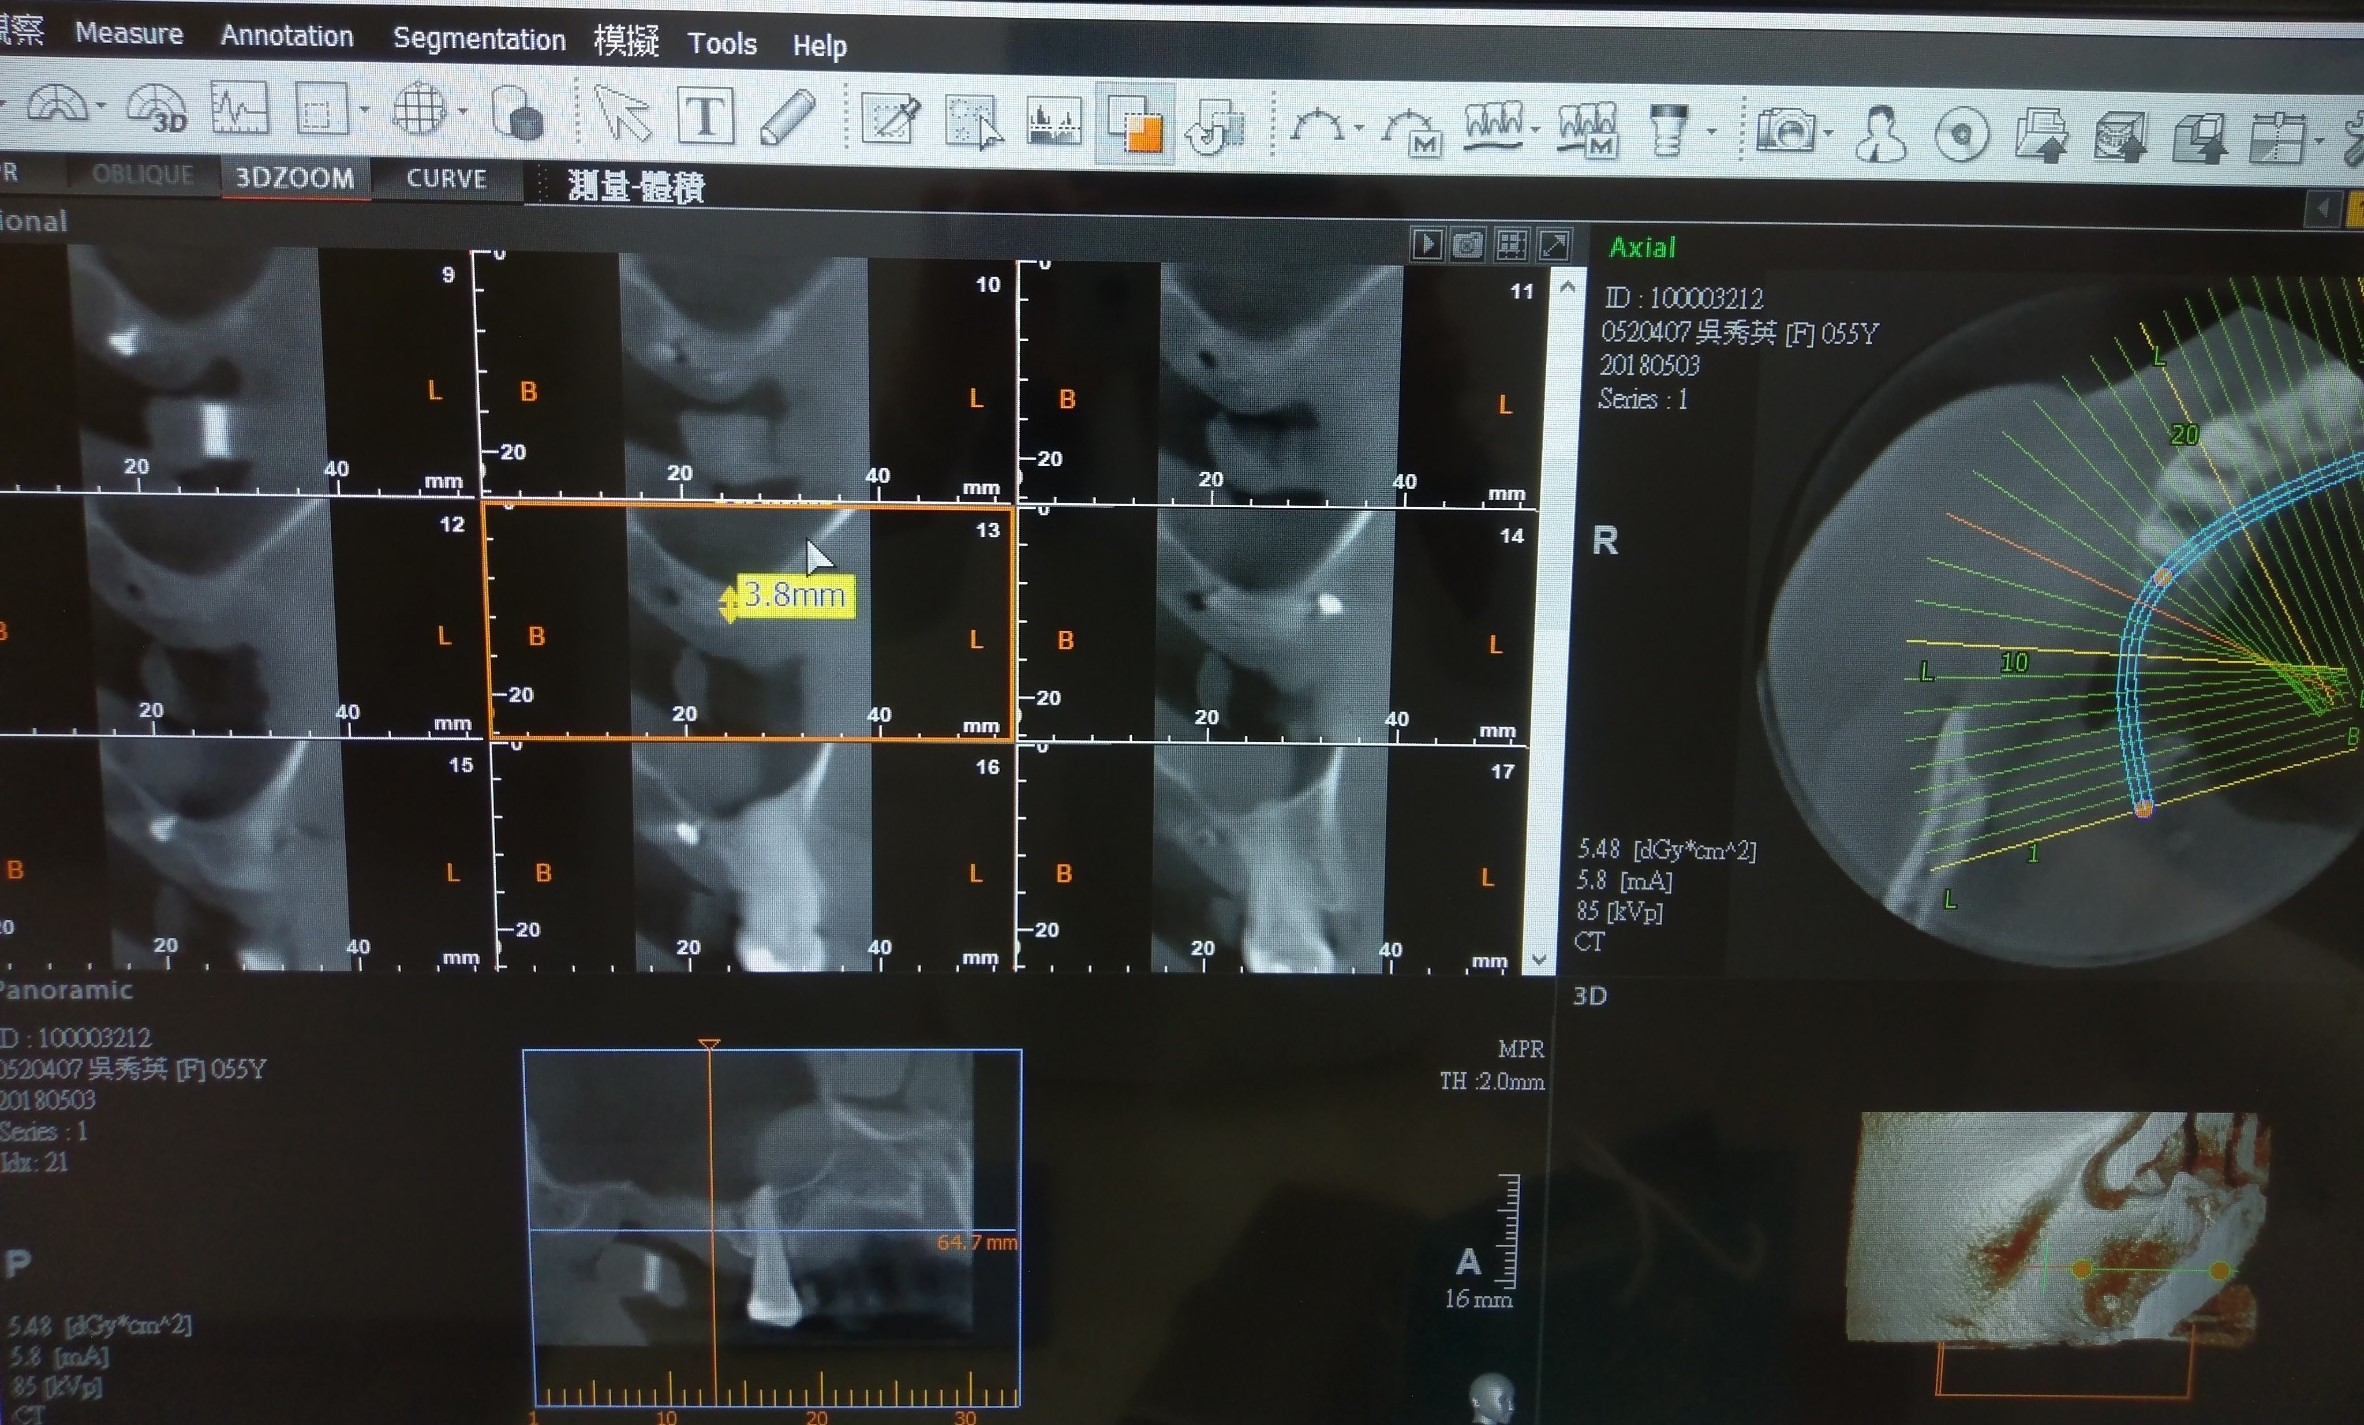

植牙+鼻竇增高手術**一次完成

人工植牙